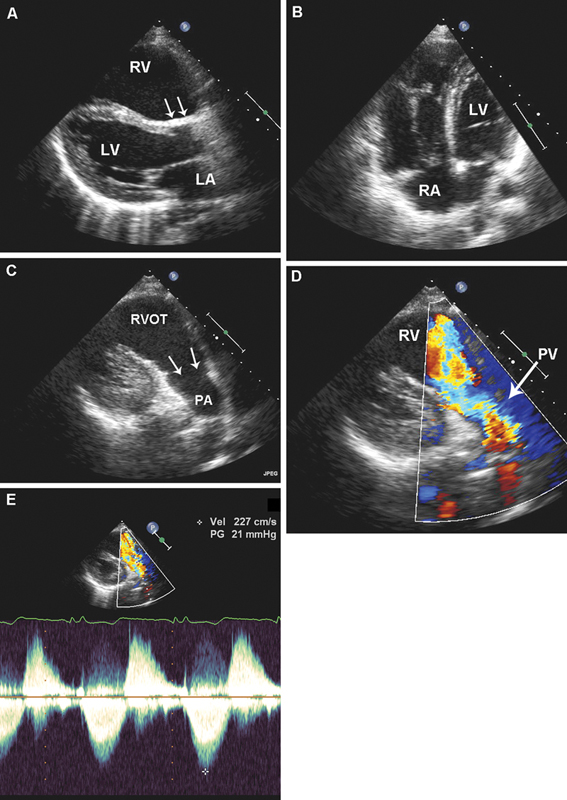

فحوصات تشخيصية لبعض امراض القلب والشرايين التاجية